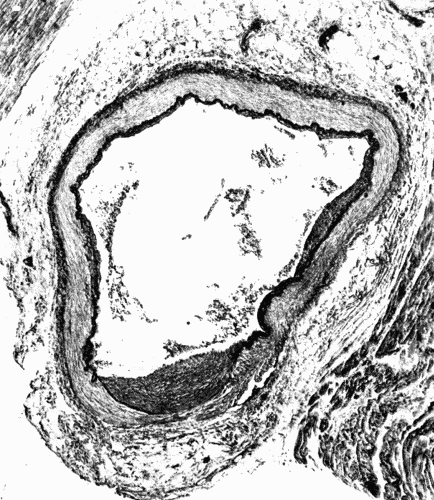

Fig. 1.—Cross section of a large artery showing the division into the three coats; intima, media, adventitia. The intima is a thin line composed of endothelial cells. The wavy elastic lamina is well seen. The thick middle coat is composed of muscle fibers and fibroelastic tissue. The loose tissue on the outer (lower portion of cut) side of the media is the adventitia. (Microphotograph, highly magnified.) Fig. 1.—Cross section of a large artery showing the division into the three coats; intima, media, adventitia. The intima is a thin line composed of endothelial cells. The wavy elastic lamina is well seen. The thick middle coat is composed of muscle fibers and fibroelastic tissue. The loose tissue on the outer (lower portion of cut) side of the media is the adventitia. (Microphotograph, highly magnified.)

Fig. 2.—Cross section of a coronary artery, ×50, showing nodular sclerosis. Note the heaping up of cells in the intima, the fracture of the elastica, and the destruction of the media beneath the nodule. The primary lesion evidently was in the media. The thickened intima is the effort on the part of nature to heal the breach. At such places as shown here aneurysms may form. (Microphotograph.) Fig. 2.—Cross section of a coronary artery, ×50, showing nodular sclerosis. Note the heaping up of cells in the intima, the fracture of the elastica, and the destruction of the media beneath the nodule. The primary lesion evidently was in the media. The thickened intima is the effort on the part of nature to heal the breach. At such places as shown here aneurysms may form. (Microphotograph.)